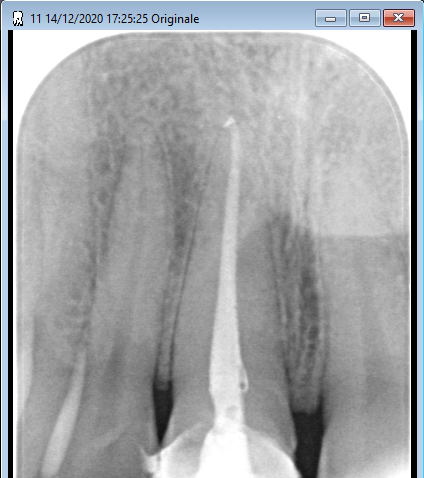

Ici c'est prévu sur cette 11, derrière je fais une CCC.